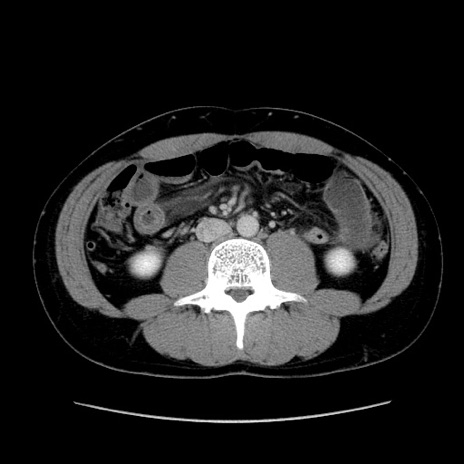

冠状断像

【症例】20歳代 男性

【主訴】心窩部痛

【現病歴】今朝より上腹部痛あり。一旦軽快していたが再度出現したため救急要請。昨日夕に白身の魚を含む刺身を食べた。

【身体所見】BP 136/89mmHg、HR 74/min、BT 37.0℃、腹部:膨満、軟、心窩部に圧痛あり。反跳痛なし、筋性防御なし、腸雑音やや亢進あり。

【データ】WBC 17700、CRP 0.48